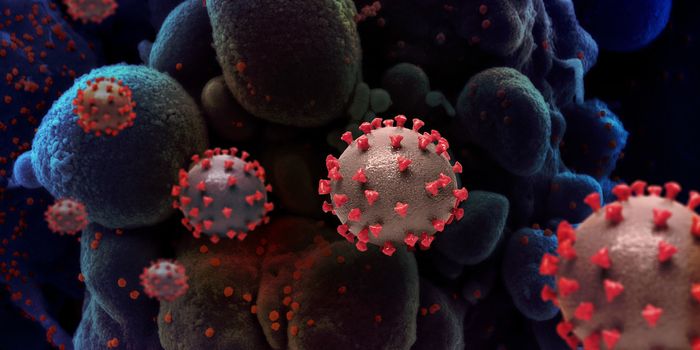

AUG 19, 2020Cell & Molecular BiologyAs the pandemic virus, SARS-CoV-2 continues to cause tens of thousands of new cases of COVID-19 every day in the United ...

APR 27, 2020MicrobiologyThe pandemic virus that causes COVID-19 has now infected nearly 3 million people, and killed over 200,000.

MAY 10, 2021MicrobiologyThe pandemic virus SARS-CoV-2 has changed the world in devastating ways, taking hundreds of thousands of lives & new var ...

MAR 03, 2020MicrobiologyThere have now been nine deaths in the United States, all in Washington state from COVID-19, the illness caused by the n ...

NOV 01, 2020MicrobiologySARS-CoV-2, which causes COVID-19 has to get into cells to cause infection. It does so with a spike protein on its surfa ...

SEP 23, 2020Cell & Molecular BiologyIn order to infect a cell, the SARS-CoV-2 virus has to find a way in. It can use receptors on the surface of cells that ...